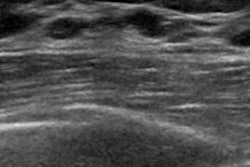

Pistolese and colleagues sought to evaluate the validity of the BI-RADS 3 category in ultrasound by using cytologic and histologic results as the reference standard. The researchers included 122 patients with 122 nodular lesions found on breast ultrasound and classified as BI-RADS 3, all of which were biopsied percutaneously (Ultrasound Med Biol, October 17, 2018).

In 86 cases (70.5%), the biopsies showed benign results; 29 cases (23.7%) had uncertain results and seven (5.7%) had malignant results. Some of these malignant lesions had cysts or small anechoic components that have typically been associated with benign lesions, according to Pistolese's team.

The presence of these typically benign characteristics in malignant lesions -- as well as the higher than expected malignancy rate -- surprised the researchers and led them to believe that the BI-RADS 3 category for ultrasound may need to be revised.